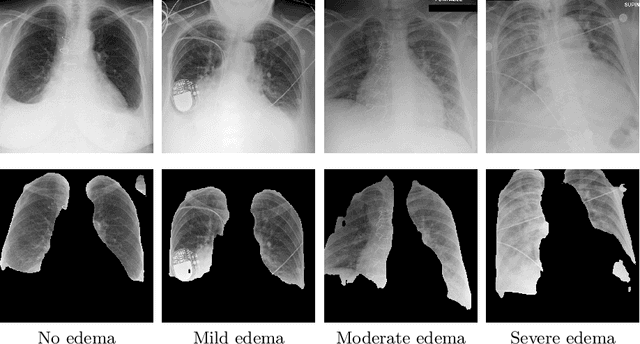

Abstract:Adoption of machine learning models in healthcare requires end users' trust in the system. Models that provide additional supportive evidence for their predictions promise to facilitate adoption. We define consistent evidence to be both compatible and sufficient with respect to model predictions. We propose measures of model inconsistency and regularizers that promote more consistent evidence. We demonstrate our ideas in the context of edema severity grading from chest radiographs. We demonstrate empirically that consistent models provide competitive performance while supporting interpretation.

Abstract:We propose and demonstrate a novel machine learning algorithm that assesses pulmonary edema severity from chest radiographs. While large publicly available datasets of chest radiographs and free-text radiology reports exist, only limited numerical edema severity labels can be extracted from radiology reports. This is a significant challenge in learning such models for image classification. To take advantage of the rich information present in the radiology reports, we develop a neural network model that is trained on both images and free-text to assess pulmonary edema severity from chest radiographs at inference time. Our experimental results suggest that the joint image-text representation learning improves the performance of pulmonary edema assessment compared to a supervised model trained on images only. We also show the use of the text for explaining the image classification by the joint model. To the best of our knowledge, our approach is the first to leverage free-text radiology reports for improving the image model performance in this application. Our code is available at https://github.com/RayRuizhiLiao/joint_chestxray.

Abstract:We propose and demonstrate machine learning algorithms to assess the severity of pulmonary edema in chest x-ray images of congestive heart failure patients. Accurate assessment of pulmonary edema in heart failure is critical when making treatment and disposition decisions. Our work is grounded in a large-scale clinical dataset of over 300,000 x-ray images with associated radiology reports. While edema severity labels can be extracted unambiguously from a small fraction of the radiology reports, accurate annotation is challenging in most cases. To take advantage of the unlabeled images, we develop a Bayesian model that includes a variational auto-encoder for learning a latent representation from the entire image set trained jointly with a regressor that employs this representation for predicting pulmonary edema severity. Our experimental results suggest that modeling the distribution of images jointly with the limited labels improves the accuracy of pulmonary edema scoring compared to a strictly supervised approach. To the best of our knowledge, this is the first attempt to employ machine learning algorithms to automatically and quantitatively assess the severity of pulmonary edema in chest x-ray images.